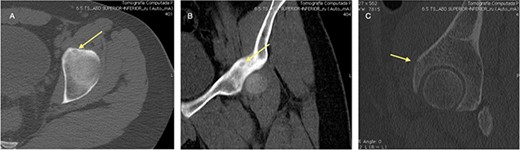

The procedure was made with general anesthesia and in supine position. A 1-cm incision was made for an anterior approach over the hip joint. Careful blunt dissection was done. Percutaneous technique was used with the guidance of a 64 slice Somatom sensation CT scanner (Siemens AG Munich, Germany) with interval cuts of 2 mm to locate the OO. Intravenous contrast was administered to identify the vascular structures at risk (Fig. 3). A 13G × 100 mm bone marrow biopsy needle was used. Image guidance was performed by a senior radiologist (ES). Once the OO was located, accurate insertion of the needle was monitored, and drilling was done manually to help precision in depth (Fig. 4). Multiple bone fragments were obtained and sampled. Immediate image verification showed a space missing the nidus OO. To avoid leaving remnant nidus, curettage was added on the edges and the deep margin of the tumor. Bone samples were sent to histological evaluation and OO diagnosis was confirmed. Wound pain management was administered for 2 weeks and night symptoms disappeared immediately. Complete relief was achieved 3 weeks later. A 12-month follow-up post treatment reported no recurrence of pain and no complications with wound management. ROM and athletic activities are painless. No soft tissue complications were reported.

CT with intravenous contrast showing the femoral vessel (yellow arrow) before the procedure to obtain proper approach (red arrow showing the OO).

CT showing the precise site for needle insertion (A), CT control of the needle insertion (B,C).